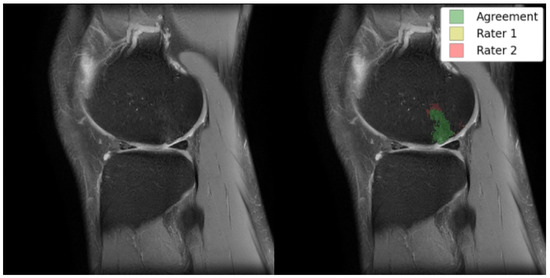

Figure 4. (a) Sample inputs (top row), (b) outputs (middle row), and (c) targets (bottom row) for each of the three tasks from left to right: slice translation; bone inpainting; and bone translation.

For the sequence translation task shown in Figure 4a, DESS is the input sequence and TSE is the output sequence. During training, the model gets a full view of the input DESS image and learns to synthesize the corresponding TSE image. Since these images are co-registered and most structures are consistent across the sequences, the model can learn this task. Furthermore, the training dataset only consists of healthy, BMEL-free images, which means the model will always synthesize a healthy TSE image given any DESS image, even if the real TSE image contains a BMEL. Therefore, DESS is the preferred input sequence since it has low signal intensity difference in healthy and BMEL regions; healthy and unhealthy DESS images look similar. Conversely, TSE is the preferred output sequence since it has high signal intensity difference in healthy and BMEL regions. The resulting anomaly map is computed by taking the difference between the real unhealthy TSE image and the fake healthy TSE image.

For the bone inpainting task shown in Figure 4b, both input and output sequences are TSE, except the input image has its bone regions removed using the bone segmentation masks. To reconstruct the full TSE image as output, the model learns to inpaint the bone given the surrounding regions, such as cartilage, muscle, etc. Again, the model is trained only on healthy images, which means it will inpaint a healthy bone region whether or not the real bone region contains BMEL or not. The bone mask is a suitable region to inpaint because by definition, BMEL occur inside the bone region and will always be inpainted.

Another task, called the bone translation task shown in Figure 4c, is also considered. In this case, only the bone regions of both DESS and TSE sequences are kept; non-bone regions are masked out using the bone segmentation mask. After this step, the task proceeds like sequence translation: DESS sequence is the input and TSE sequence is the output. This task may have the advantage of removing confounding factors in the surrounding regions around the bone that may not be relevant to the generation of the anomaly map.